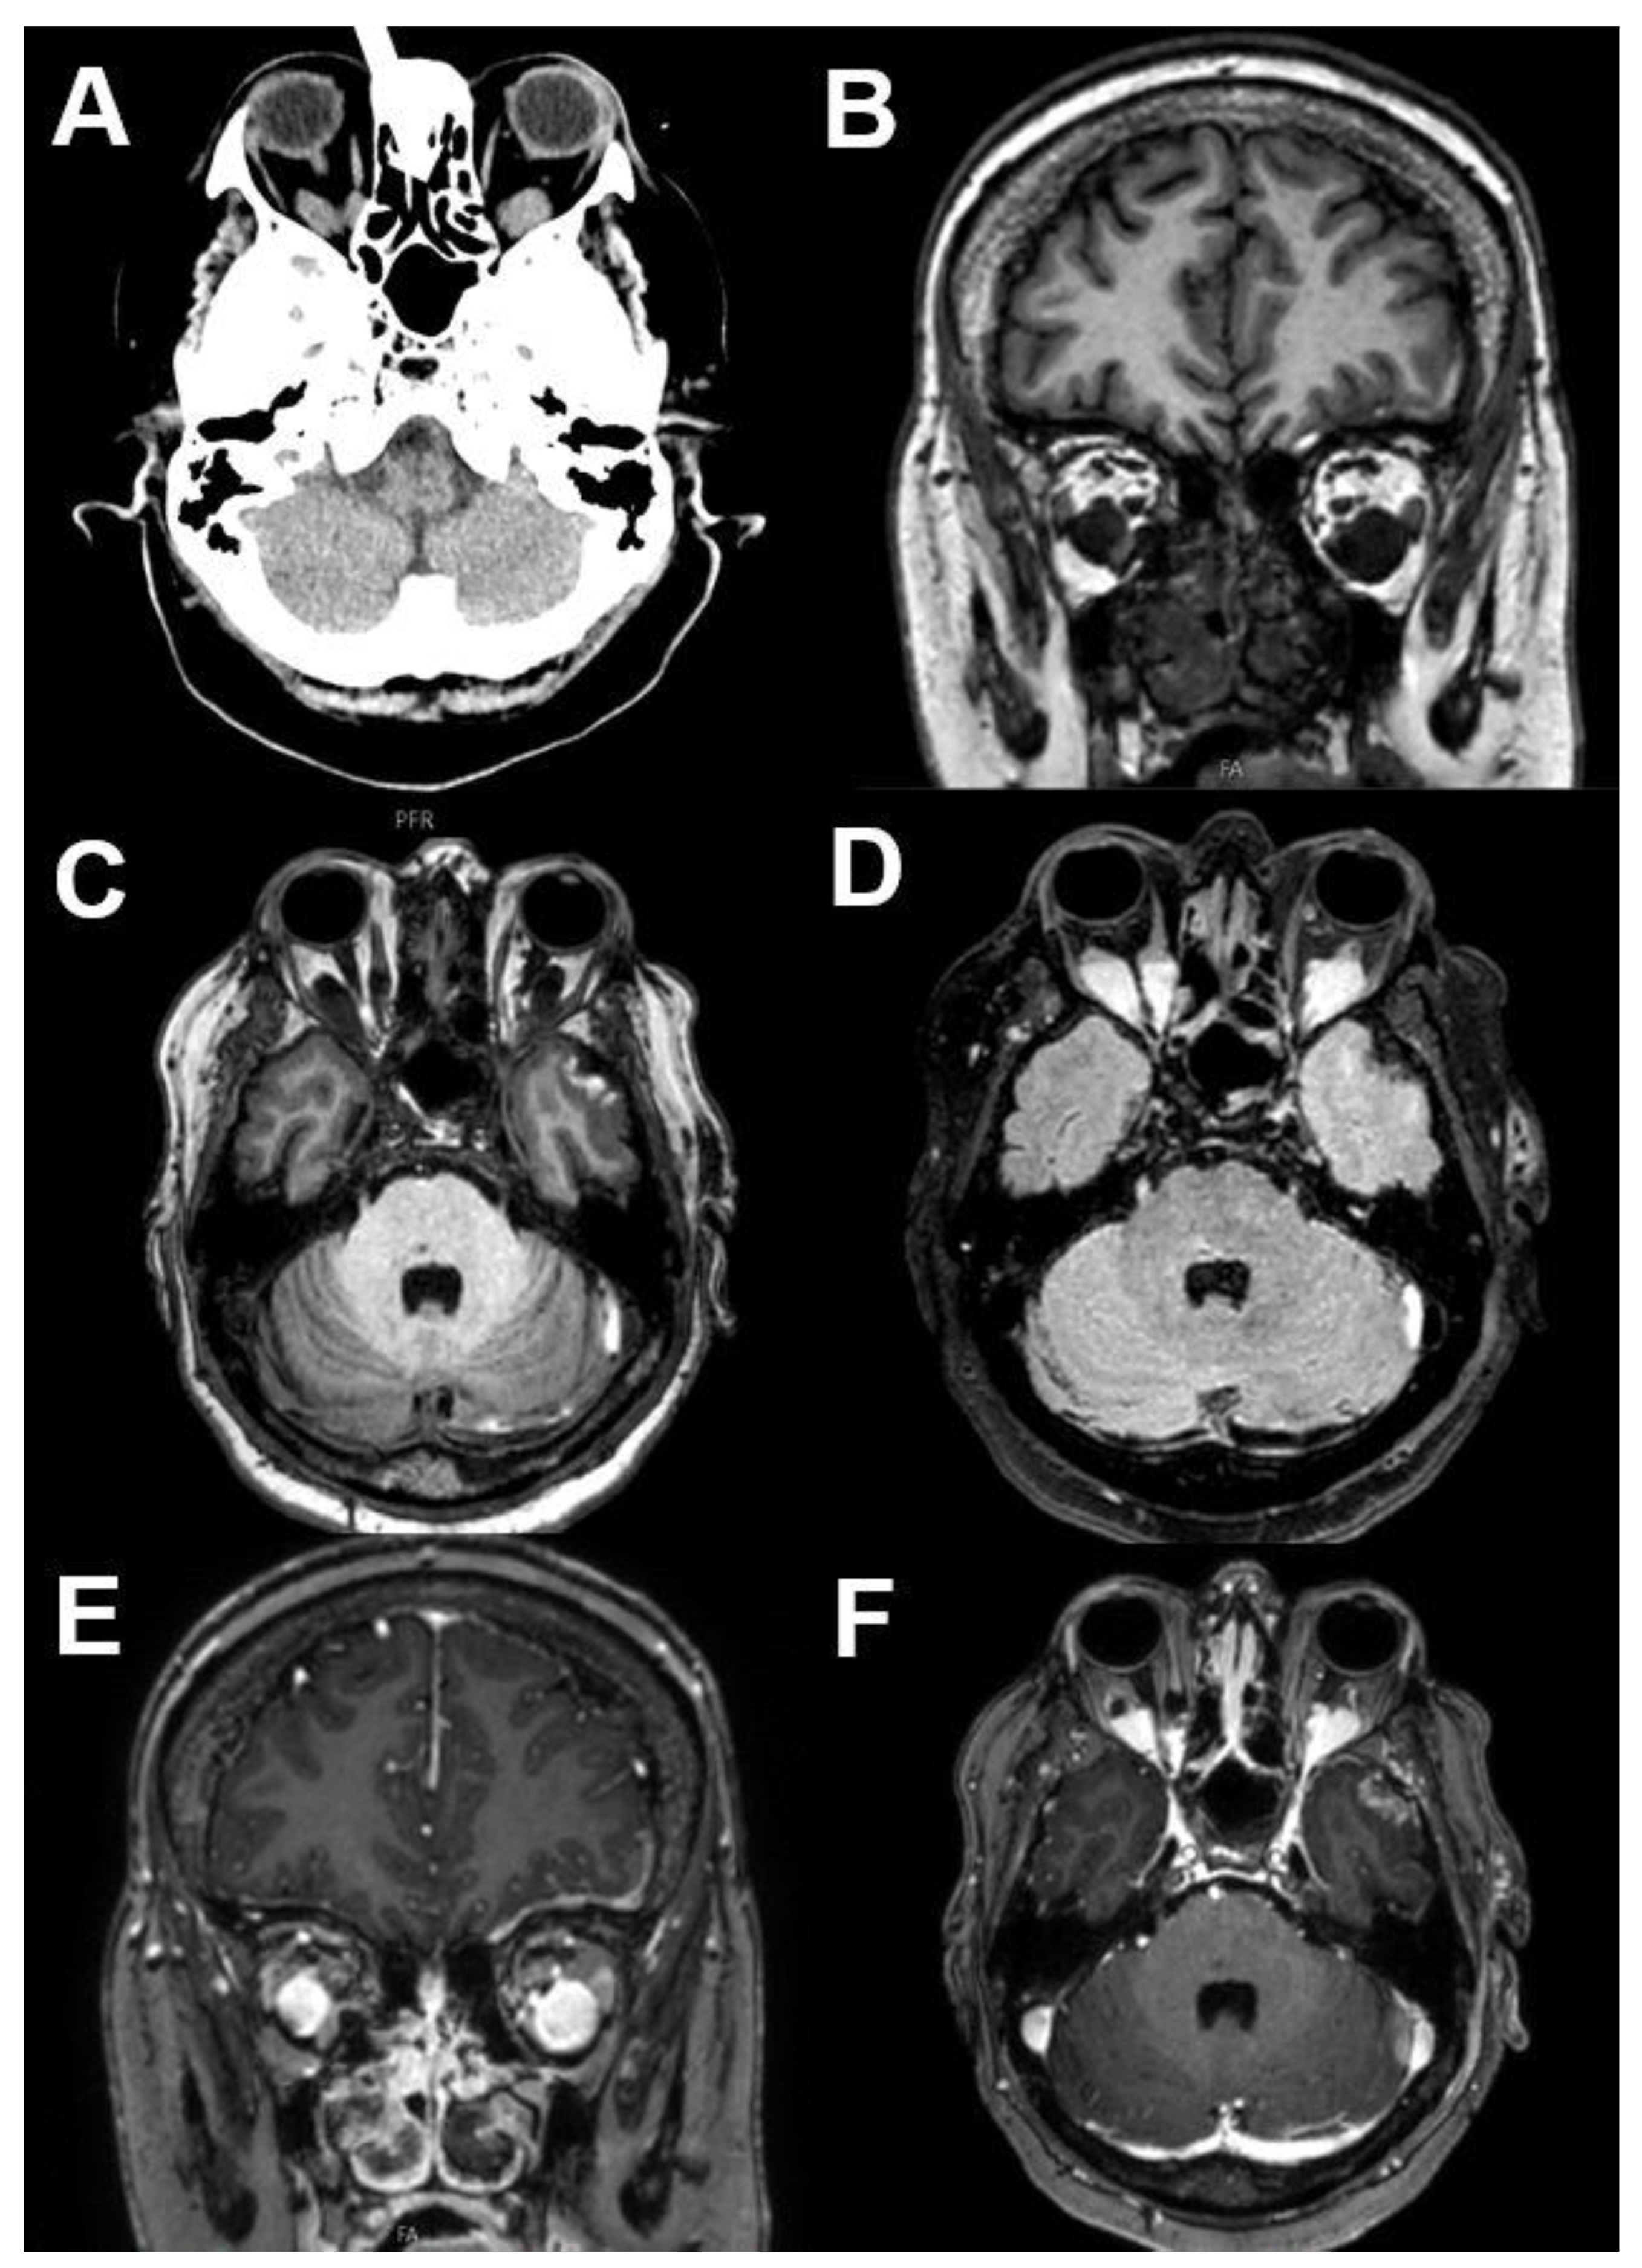

3.2. Intraconal Tumors

3.2.1. Venous Varices

3.2.2. Cavernous Hemangioma

3.6.2. Rhabdomyosarcoma